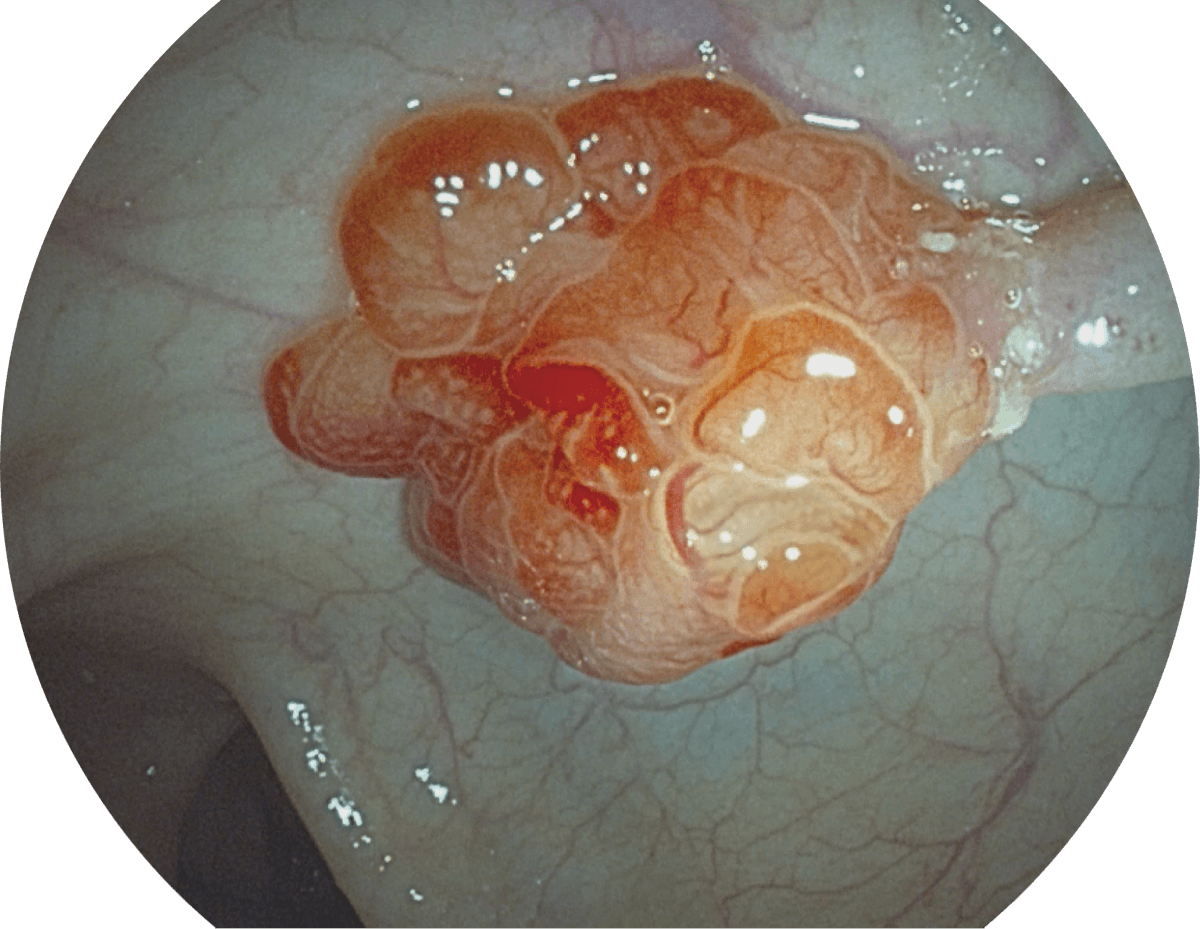

具有聚谱成像技术(SFI)及光电复合染色成像技术(VIST),可完美呈现粘膜细节及病变特征。

( Versatile Intelligent Staining Technology, VIST )

VIST